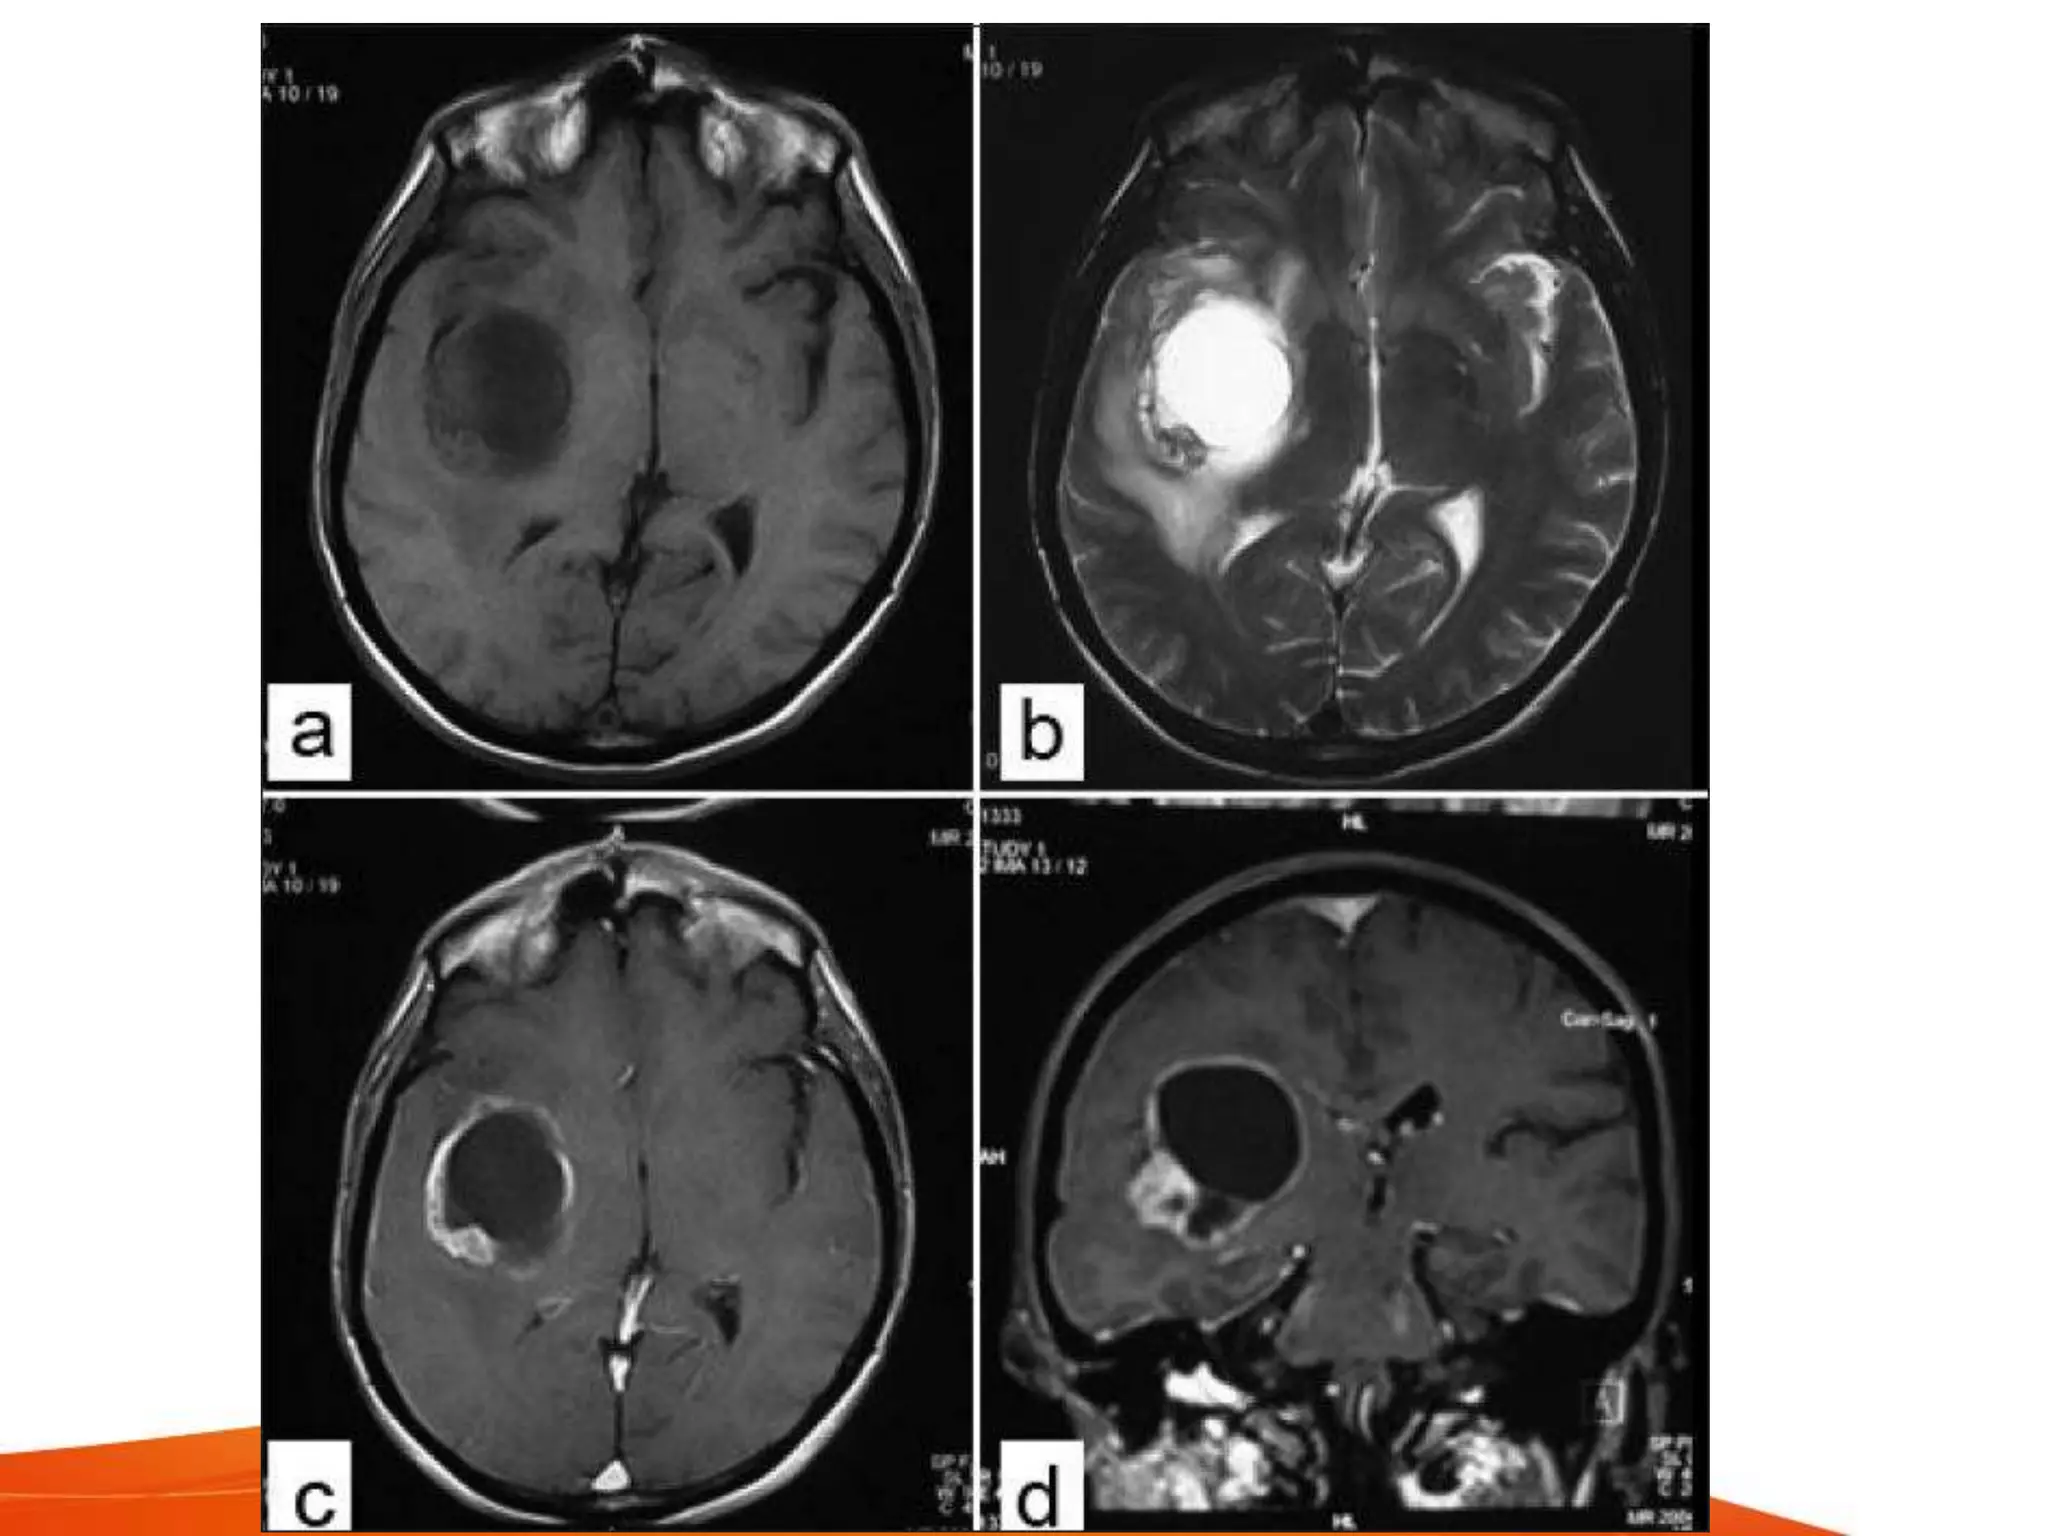

MRI

• more sensitive in

– early cerebritis

– extent of central liquefaction necrosis

– early satellite lesions

– extraparenchymal extension (subdural

empyema)

• insentive to differentiate

– cystic or necrotic high grade glioma

– metastasis

• T1 - pus is hypointense

• T2 - pus is hyperintense

• FLAIR - nullifies free water signal, caused

by increased protein content

– reported in brain tumors, abscesses and

vascular insults

• Diffusion weighted imaging (DWI) and

apparent diffusion coefficient (ADC) -

based on movements of water molecules

– to measure degree of water movements, ADC

maps are useful

– abscess contains bacteria, proteins and pus.

Hence shows restricted water motion

– DWI shows incresed signal with low ADC

values

– most necrotic tumors have serous fluid and

fewer inflammatory cells. Hence shows low-

intermediate intensity on DWI and high ADC

values due to serous fluid